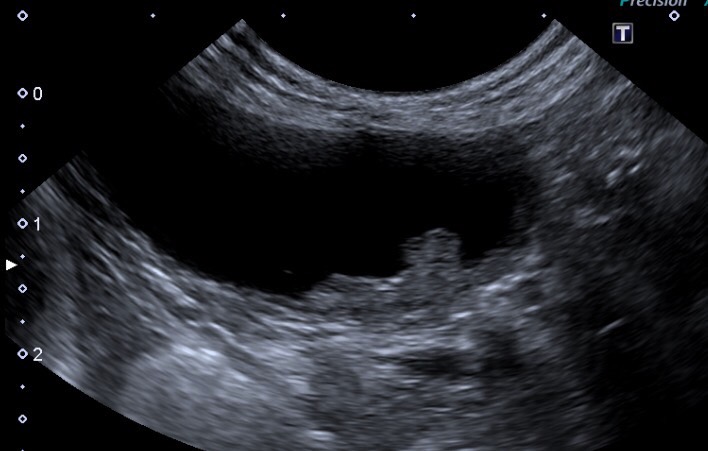

写真:超音波検査で観察された膀胱移行上皮癌

膀胱移行上皮癌が疑わしい場合は、細胞診検査や遺伝子検査、膀胱鏡検査など追加の精密検査を受け、治療方法を選択できるように正しく診断していきましょう。